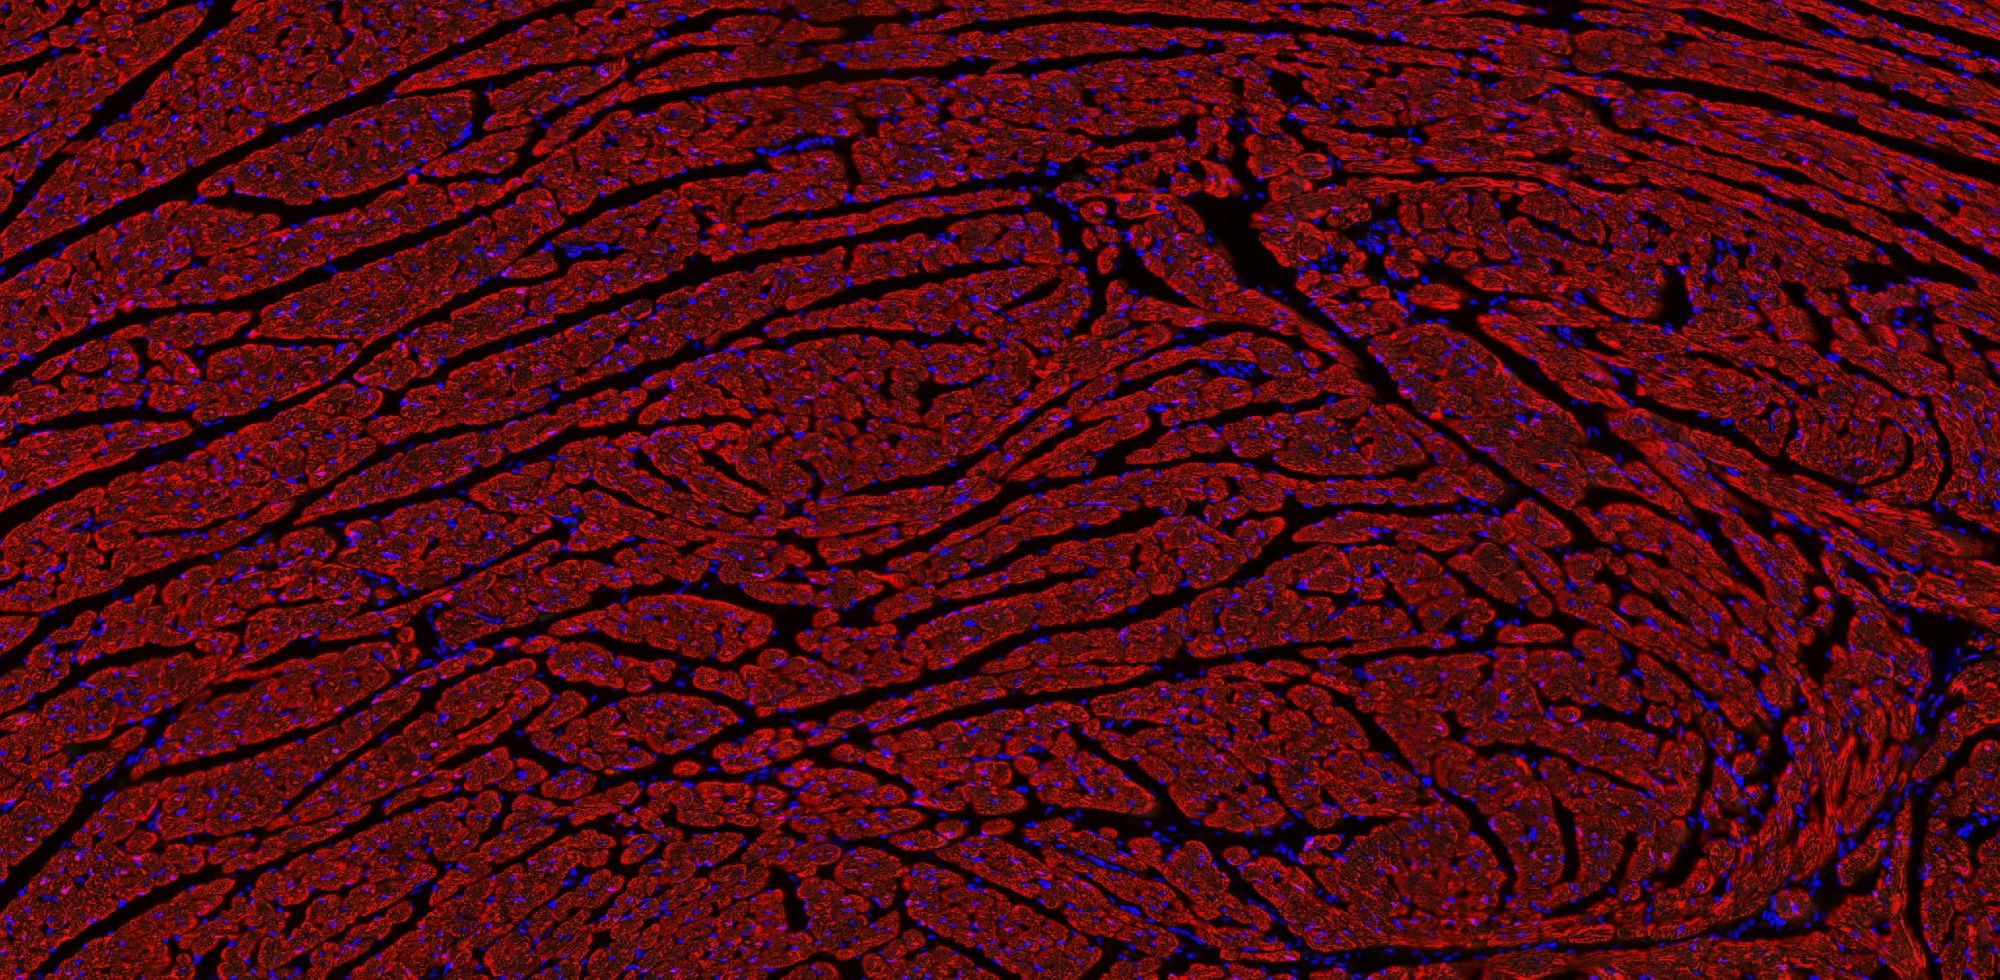

【技術(shù)原理】

免疫學(xué)的基本反應(yīng)是抗原-抗體反應(yīng)。由于抗原抗體反應(yīng)具有高度的特異性,所以當(dāng)抗原抗體發(fā)生反應(yīng)時(shí),只要知道其中的一個(gè)因素,就可以查出另一個(gè)因素。免疫熒光技術(shù)就是將不影響抗原抗體活性的熒光色素標(biāo)記在抗體(或抗原)上,與其相應(yīng)的抗原(或抗體)結(jié)合后,在熒光顯微鏡下呈現(xiàn)一種特異性熒光反應(yīng)。

案例展示